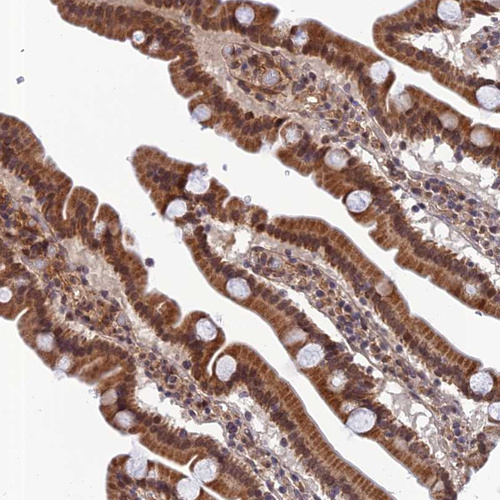

Immunohistochemical staining of human pancreas shows moderate cytoplasmic positivity in exocrine glandular cells.